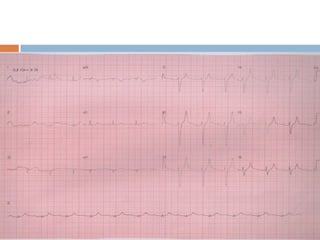

   ELETROCARDIOGRAMA

EXAMES COMPLEMENTARES  ELETROCARDIOGRAMA  CARDIOESTIMULAÇÃO TRANSESOFÁGICA  TESTE ERGOMÉTRICO  HOLTER  LOOPER  ECG DE ALTA RESOLUÇÃO  TESTE DE INCLINAÇÃO ORTOSTÁTICA (TILT TEST)  ECOCARDIOGRAMA ( TT OU TE )  RAIO X DO TÓRAX  BIOQUÍMICA  SOROLOGIAS  RESSONÂNCIA NUCLEAR MAGNÉTICA  ANGIOTOMOGRAFIA DAS CORONÁRIAS  ESTUDO ELETROFISIOLÓGICO ( INVASIVO )